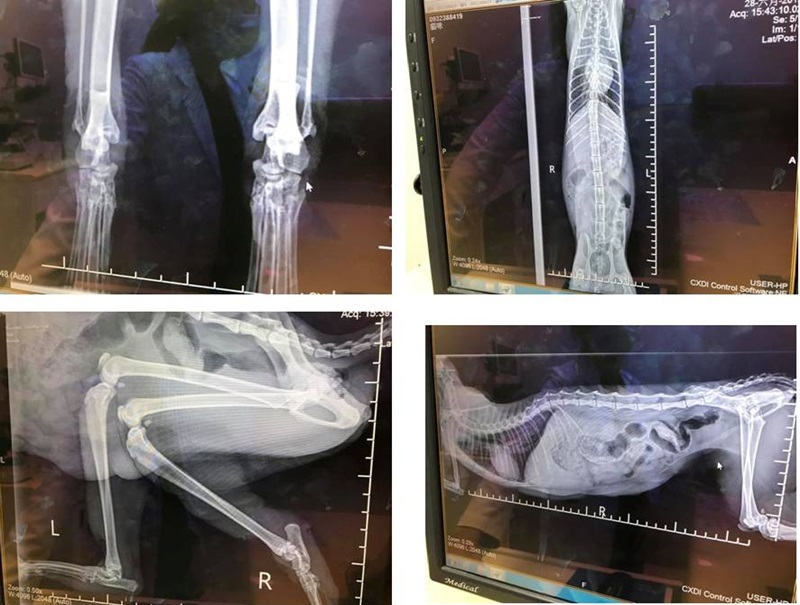

1. 貓咪後肢已嚴重痿縮、壞死,已散發強烈腐肉味道,末端皆已乾涸。

2. 28日下午2點貓咪腳掌雖壞死、但仍連結與腳骨上,依x光片判讀,膝蓋骨以下骨質結構已完全變形。

3.依壞死狀況需截肢,依貓目前狀況,再拖下去不處理或清創,都可能造成感染與傷害。

06/29 協會工作人員帶著小酒窩到亞太醫院進行兩側後肢截肢手術,到了醫院將她抱出外出籠時,赫然發現原本還在的腳掌竟然已自行斷掉,大家還找半天,應是掉落在汎亞動物醫院,見此狀大家莫不感到無比心疼。

術前血檢的結果,小酒窩的紅血球掉很快,血溶比從27日的27.5% 掉至18.9%,顯示傷口對健康已造成極大影響,若不及時處理,可能引發敗血、感染。

小酒窩在當日晚間19:30完成雙側後肢截肢手術,手術順利,術後貓咪2.1公斤、狀況穩定,由協會自行帶回術後觀察與照護。